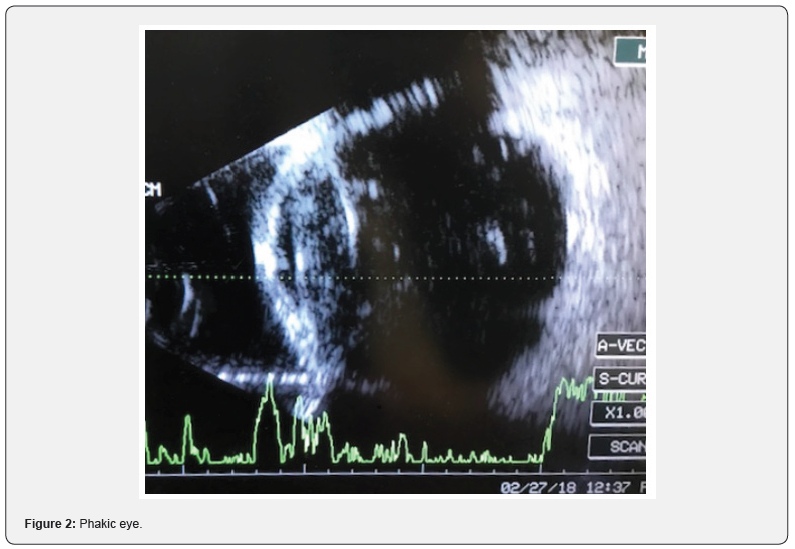

A 61 year-old man presented for examination with progressive visual loss on left eye, pain and cephalea for 4 weeks. He has previous history of Primary Open Angle Glaucoma under treatment with dorzolamide-timolol. He also refers LASER treatment on the left eye to treat a retinal detachment four months before in another institution. On ophthalmological examination the right eye had mild lens opacity, IOP 20mmHG, VA 20/60, open angle Shaffer- 4 classification and an optic nerve excavation of 7/10. The left eye had conjunctival hyperemia, corneal sub-epithelial edema, grade 2 flat anterior chamber, mild lens opacity, IOP 42 mmHg, and VA of hand movement. Fundoscopy was not possible due to media opacity (Figure 1). Ultrasound B-scan reported a phakic eye, dense vitreous hemorrhage, whereas the retina and choroid were intact and flat (Figure 2).